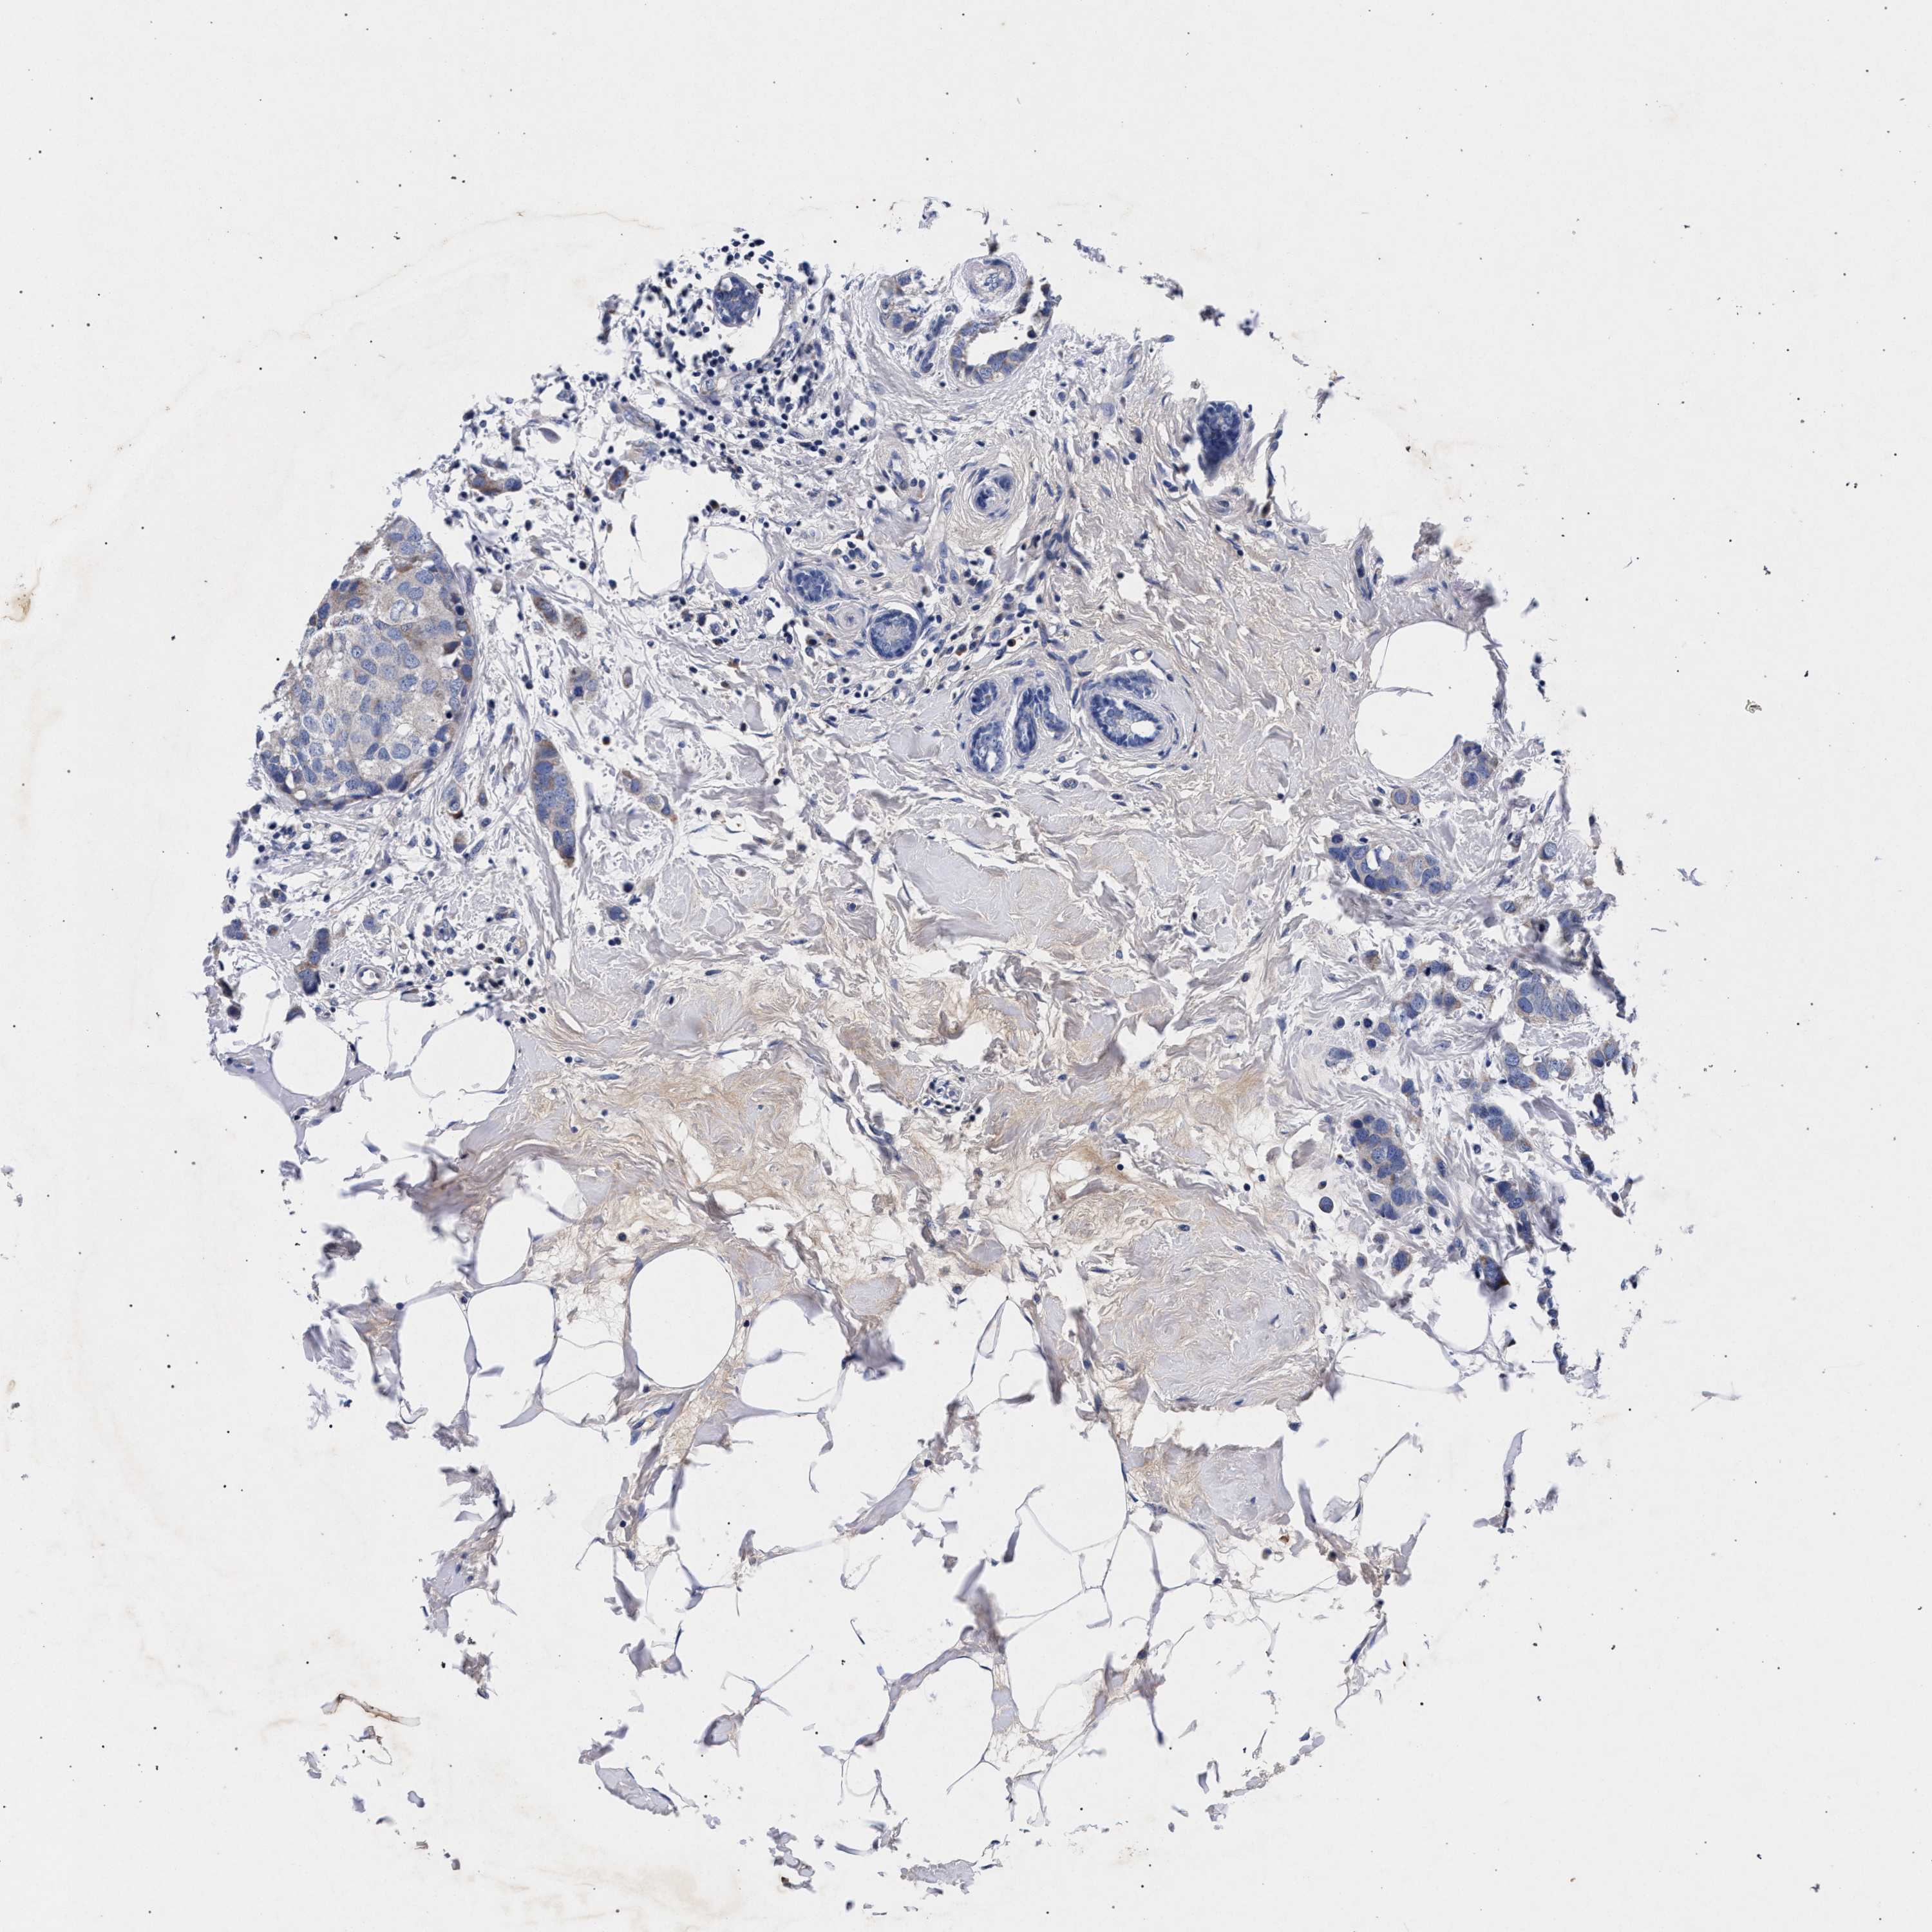

BRCA TCGA BRCA VALIDATION PROTEIN EXPRESSION

ANTIBODIES

AND

VALIDATION